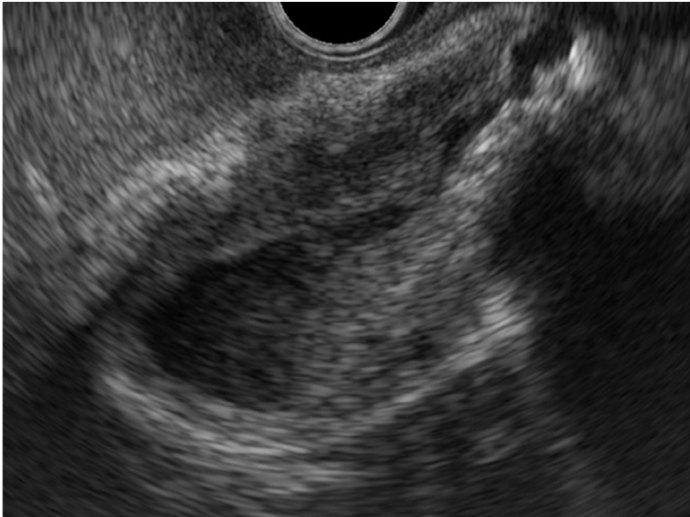

El diagnóstico se realiza preferiblemente mediante tomografía computarizada, con hallazgos característicos como un ángulo aortomesentérico menor de 22° y una distancia entre vasos menor de 8 mm (25). La endoscopia digestiva alta puede ser útil en las etapas iniciales, aunque por sí sola no es concluyente. Kim et al. (26) describieron tres hallazgos endoscópicos indirectos sugestivos de pinzamiento aortomesentérico:

- Compresión pulsátil vertical u oblicua en la tercera porción del duodeno con una expansión luminal inferior al 30 % incluso tras una insuflación continua durante 15 segundos

- Dilatación del duodeno proximal

- Presencia de secreción biliar en la cavidad gástrica